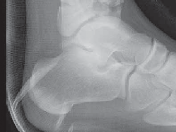

5.

The diagnosis of tibial plafond fracture is initially evaluated with three radiographic views of the ankle (anteroposterior [AP], mortise, and lateral; FIG 4A,B).

CT scans have been clearly shown to improve a surgeon’s understanding of the injury ( FIG 4C) and are critical to preoperative planning for complex injuries.15

7.

For displaced, comminuted pilon fractures, the best time to obtain a CT scan is after temporizing external fixation is performed ( FIG 4D), when the fracture is brought out to length with traction. This tends to grossly reduce many parts of the fracture, making the pathoanatomy of the injury more understandable (FIG 4E,F).

E F ### FIG 4 • 43-C3 tibial plafond injury. A,B. AP and lateral injury radiographs. C. CT scan. D. “Travelling traction”—early ankle-spanning external fixator. E,F. Radiographs of ankle after closed reduction and application of external fixator. G. Three-dimensional reconstruction of CT angiogram demonstrat- G ing deficient flow through anterior tibial artery.